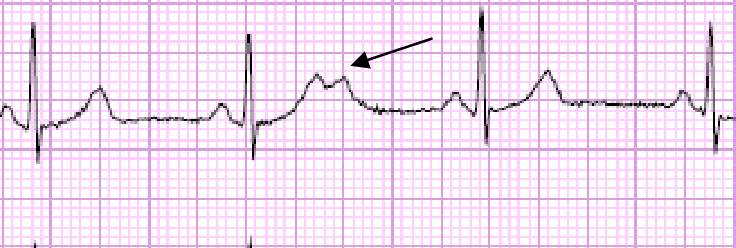

Blocked PAC due to both bundle branches are in the refractory period.

• اذا صادف أن وقت هذه النبضة حصل قبل منتصف موجة T في النبضة السابقة قد يحصل هناك توقف عن ارسال الشحنات في كلا المسارين Right /left bundle branches مما يؤدي لعدم مرور النبضة للبطين، و ينتج أن يكون فيما بعدها توقف لحظي عن ارسال الشحنات .